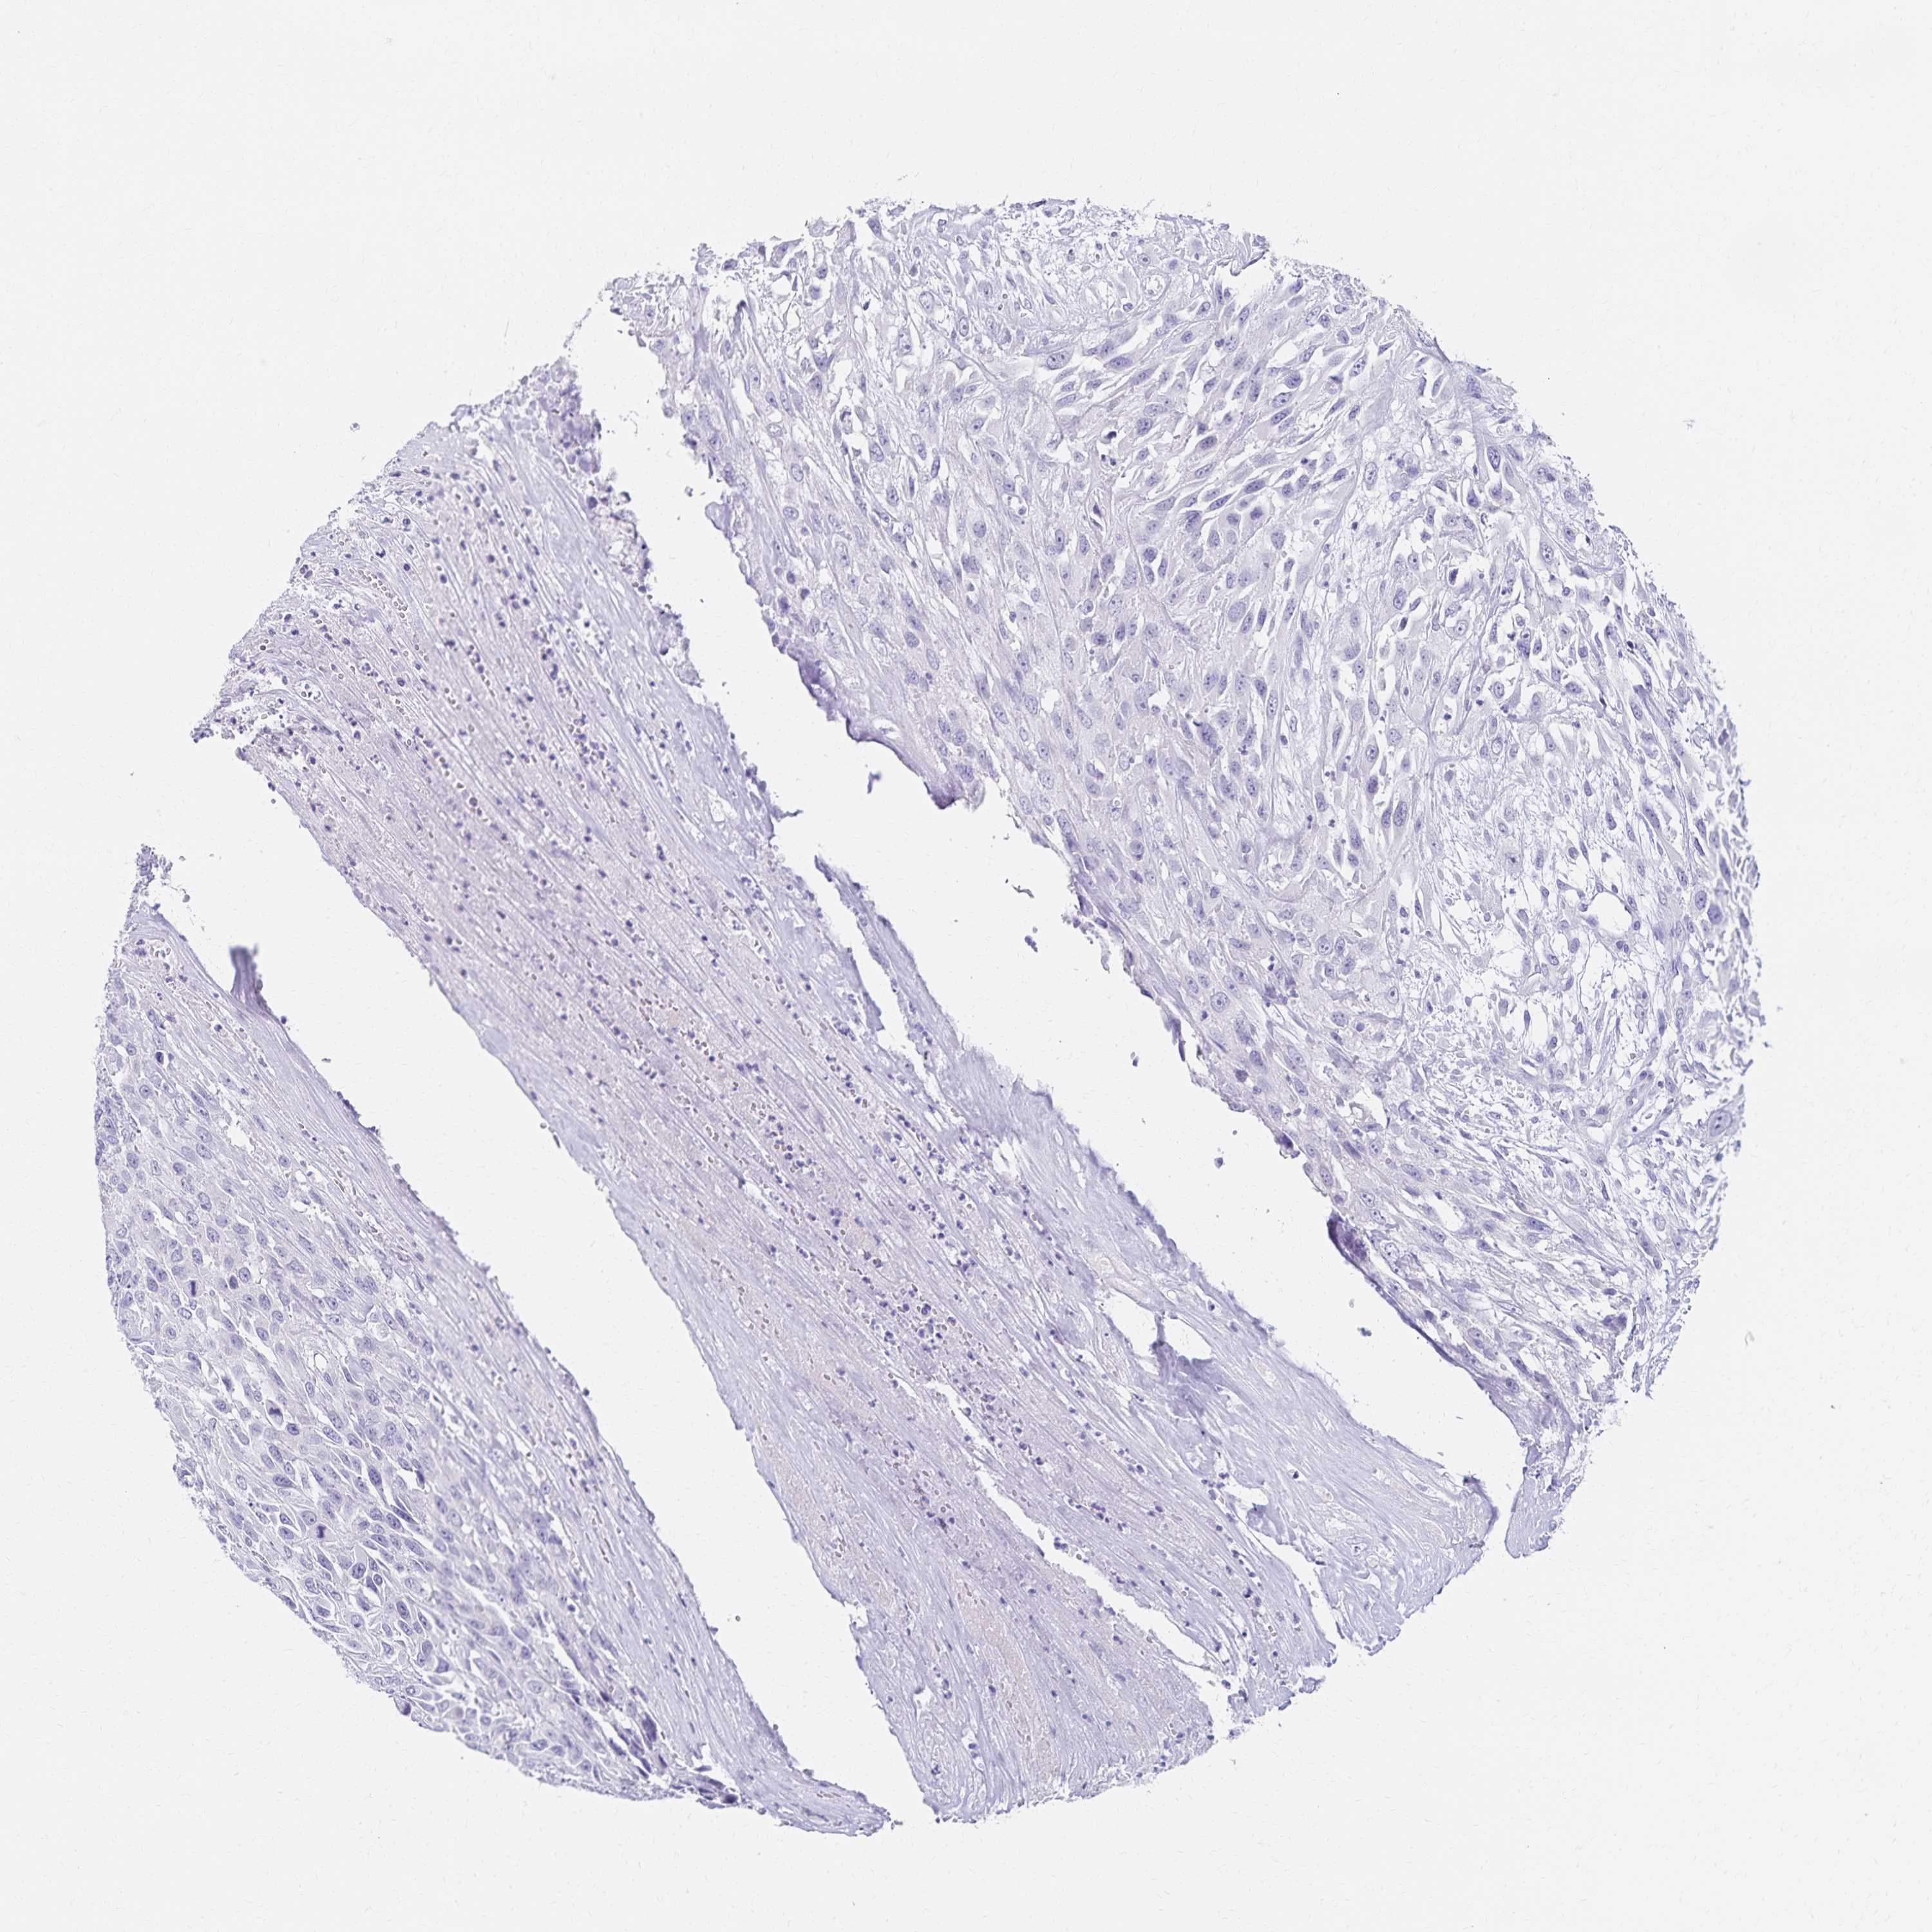

UROTHELIAL CANCER - Protein expressioni

A mouse-over function shows sample information and annotation data. Click on an image to view it in a full screen mode. Samples can be filtered based on level of antibody staining by selecting one or several of the following categories: high, medium, low and not detected. The assay and annotation is described here.

Note that samples used for immunohistochemistry by the Human Protein Atlas do not correspond to samples in the TCGA dataset.

Antibody stainingi

Antibody staining in the annotated cell types in the current human tissue is reported as not detected, low, medium, or high, based on conventional immunohistochemistry profiling in selected tissues. This score is based on the combination of the staining intensity and fraction of stained cells.

Each image is clickable and will lead to virtual microscopy that enables deeper exploration of all samples and also displays staining intensity scores, fraction scores and subcellular localization as well as patient and tissue information for each sample.

Antibody HPA062894

Staining

High

Medium

Low

Not detected

Intensity

Strong

Moderate

Weak

Negative

Quantity

>75%

75%-25%

<25%

None

Location

Nuclear

Cytoplasmic/membranous

Cytoplasmic/membranous,nuclear

Urothelial carcinoma, High grade

Urothelial carcinoma, NOS

Urothelial carcinoma, Low grade